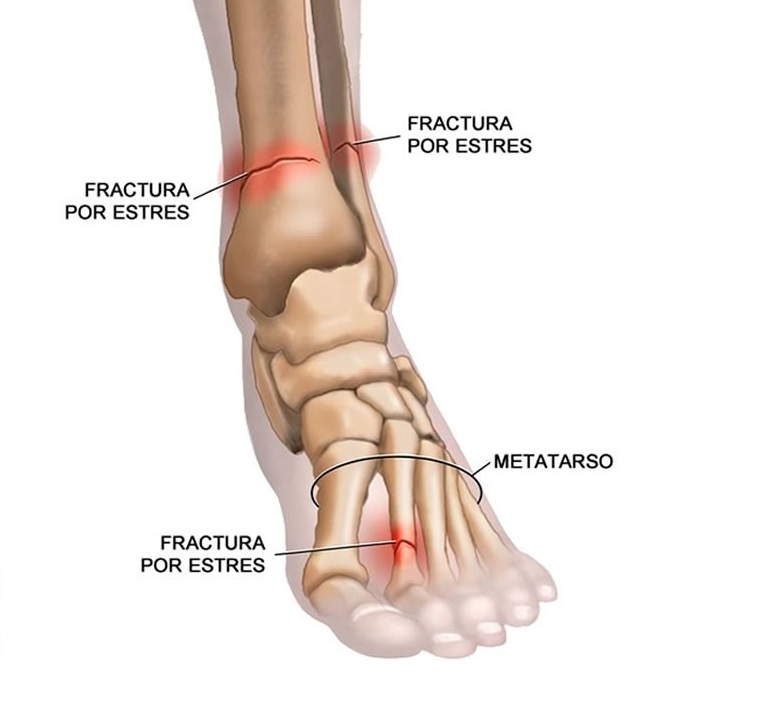

Estas fracturas pueden aparecer en distintas localizaciones, siendo la localización mas frecuente la fractura por estres de los huesos del pie También se suele denominar, fractura por fatiga Dentro de estos huesos, las zonas de más asiduidad en presencia de fracturas por estrés serían el cuello del segundo y tercer metatarso, ya que es. Las fracturas por estrés ocurren cuando usted usa su cuerpo en exceso Por lo tanto, es una lesión por uso excesivo Las fracturas por estrés pueden describirse mejor por ortopedistas que lo describen como una pequeña grieta en el hueso Las fracturas por estrés también se conocen bajo su otro nombre que es Fractura de la línea del cabello Algunas veces, también se lo conoce como Fractura de fisura. Cuando esto sucede, la tensión que normalmente se absorbería en el músculo se redirige al hueso, lo que resulta en una grieta.

La fractura por estrés metatarsiano es la ubicación más común para una fractura por estrés después de las fracturas por estrés tibial El segundo metatarso se fractura con mayor frecuencia en una fractura metatarsal, especialmente en aquellos individuos que tienen un segundo dedo del pie más largo en comparación con su dedo gordo del pie También ocurre comúnmente en aquellos individuos que sobrepronan usando el primer metatarso en una posición dorsiflexionada porque esto. 15 Gómez CLA y cols Fracturas por estrés en el atleta epidemiología y manejo wwwmedigraphicorgmx perióstica, esclerosis de las corticales y/o del canal medular o líneas sutiles que sugieran una fractura, especialmente en proyecciones laterales. Estas fracturas pueden aparecer en distintas localizaciones, siendo la localización mas frecuente la fractura por estres de los huesos del pie También se suele denominar, fractura por fatiga Dentro de estos huesos, las zonas de más asiduidad en presencia de fracturas por estrés serían el cuello del segundo y tercer metatarso, ya que es la zona que más carga recibe dentro del pie.

Tratamiento de una fractura por estrés Actualizado 10 de septiembre de Habitualmente, una fractura por estrés viene acompañada de dolor unido con la actividad, y por lo tanto, que cede con el reposo del miembro afectado. Síntomas de una fractura por estrés Normalmente se comienza sintiendo un leve dolor mientras se realiza la actividad que suele desaparecer cuando se descansa Sin embargo, después de un par de semanas, aproximadamente, el dolor se vuelve continuo incluso cuando dejas de practicar el ejercicio, siendo habitual presentar signos de inflamación. Por lo general, se presentan más frecuentemente en los pies Las fracturas por estrés suelen desarrollarse en la tibia (hueso de la espinilla), el peroné (huesos inferiores de la pierna), los metatarsos (huesos de los pies) y el navicular (huesos en la parte media del pie).

Las fracturas por estrés suelen aparecer por repetir el mismo movimiento una y otra vez (por ejemplo, cuando alguien se entrena para un deporte) También pueden aparecer por las actividades diarias en las personas con huesos débiles debido a una mala nutrición o a una afección médica. La fractura por estrés ocurre más gradualmente, durante un período de tiempo, debido al uso excesivo o impacto / trauma repetitivo en el hueso Las fracturas por estrés usualmente involucran el segundo, tercer o cuarto hueso del metatarso La fractura por estrés metatarsiano es la ubicación más común para una fractura por estrés. Qué son las fracturas por estrés Actualizado 10 de septiembre de Se considera fractura a la falta de continuidad en una estructura ósea En la mayoría de los casos, estas fracturas son consecuencia de acciones traumáticas En el caso de las fracturas por estrés, el resultado viene dado por una reiteración prolongada y repetitiva de fuerzas o micro traumatismos de bajo impacto.